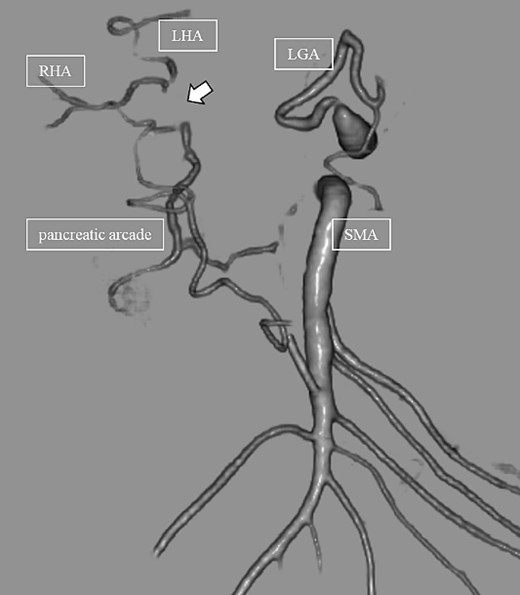

Subsequently, interventional radiology (IVR) was performed. However, because the inferior pancreaticoduodenal artery (IPDA) was very narrow, the microcatheter could not be followed, and hemostasis with IVR was difficult. Therefore, on POD 48, relaparotomy pseudoaneurysm repair was performed. The abdomen was opened through an inverted L-shaped incision, and adhesiolysis was performed, after which a pseudoaneurysm was revealed at the junction of the GDA and PHA. Four transfixing sutures with 3–0 prolene were used. After confirming that the liver blood flow was maintained, surgery was completed. However, bloody drainage from the drain was observed on POD 56. CeCT revealed a pseudoaneurysm (Fig. 3A and B). IVR was considered difficult because of the narrow blood vessels; therefore, the patient underwent a second laparotomy for hemostasis. A pseudoaneurysm was further observed at the junction between the GDA and PHA. In this operation, we used deeper and wider penetrating sutures than in the previous surgery to completely halt blood flow in the GDA. We confirmed that the blood flow to the liver was maintained; however, it was deemed weak. The patient had an uneventful postoperative course without bleeding, and CeCT performed on POD 61 confirmed the disappearance of the pseudoaneurysm. Although the blood flow in the PHA could not be confirmed, the right and left hepatic arteries were preserved (Fig. 4). On POD 76, CT revealed no liver abscesses or infarctions. The drain was removed on POD 78, and the patient was finally discharged on POD 107 without rebleeding or liver failure.

CT on postoperative Day 61. Although blood flow in the PHA could not be confirmed (arrow), the right and left hepatic arteries are preserved.